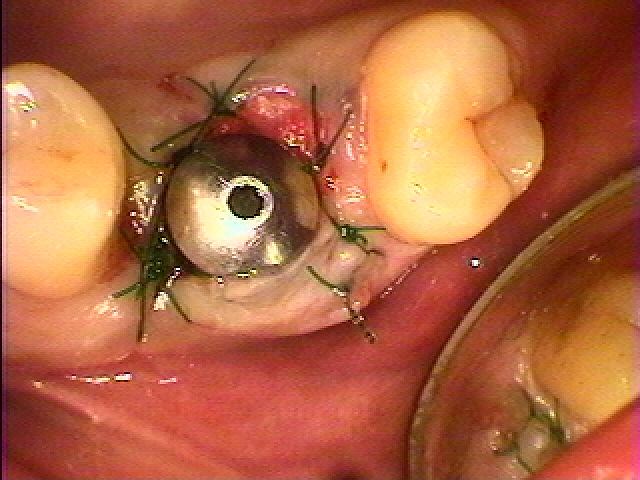

縫合して終了となります

縫合して終了となります